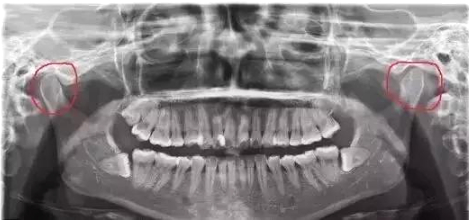

我们平时看患者的X光片的时候,就能看出来这个人是否有偏侧咀嚼的习惯,往往颞颌关节一侧大一侧小的患者都有偏侧咀嚼的习惯。

如下图